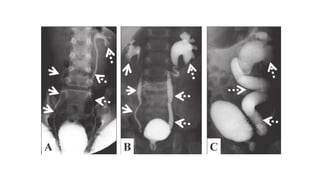

MCUG

•Done to study bladder, posterior urethra and competence of VUJ

•Film is taken during micturition / when the pt is attempting to void

• Grades of VUR

Retrograde Cystourethrography

•Useful in cases of lower tract obstruction

•Especially helpful to visualise anterior urethra